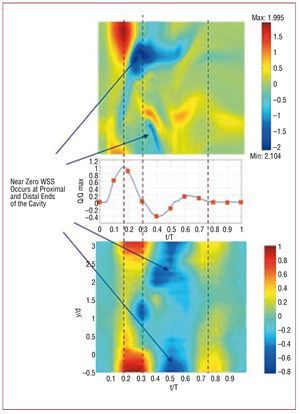

Recent experiments by Salsac et al107,109 have shown that this separation occurs even during the very early stages of aneurysm growth (a ratio of less than 1:1 between maximum diameter and parent diameter). Salsac and others,109,122 have also shown that as the aneurysm generally grows nonsymmetrically, the location and magnitude of the regions of high gradients of temporal and spatial blood flow shear stresses, as well as the extent of the regions of low, but oscillatory, shear stresses along the wall increase significantly with growth. Figure 7 shows that the results of numerically simulated blood flow agree well with the experimental measurements. Both experiments and simulations show that the aneurysm wall is subjected to abnormal WSS during the major portion of the cardiac cycle. They also show that, during diastole, the blood remains almost stagnant near the proximal and distal ends of the aneurysm where the WSS drops to near zero values.

Figure 7. Distribution of wall shear stresses (WSS) exerted by the blood flow in the abdominal aortic aneurysm shown in Figure 6. Top part, numerical simulation; bottom part, experimental measurements. The vertical axis is the position along the wall normalized by the diameter of the aorta at the proximal end of the aneurysm. The horizontal axis is time-normalized by the cardiac period. The color represents the magnitude of the blood shear stresses which have been normalized by the maximum WSS of the healthy aorta at peak systole. Observe that during diastole the WSS are near-zero in both the proximal and distal regions of the aneurysm. Adapted from Tang et al.213